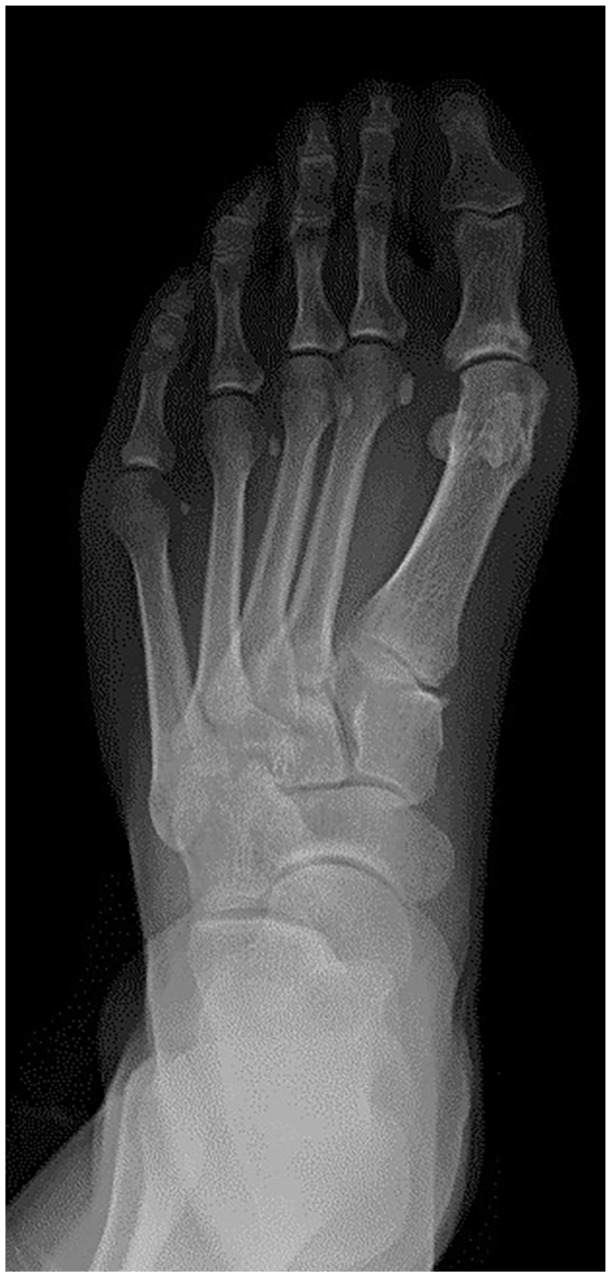

Concurrent Heuter's and Morton's Neuromata Following Hallux Valgus Surgery: A Rare Case and Review of Terminology.

Visual AbstractThis is a visual representation of the abstract.